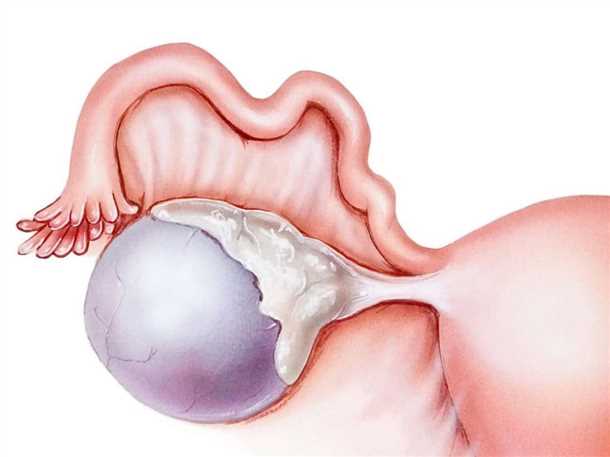

Гистологические изображения фолликулярной кисты яичника